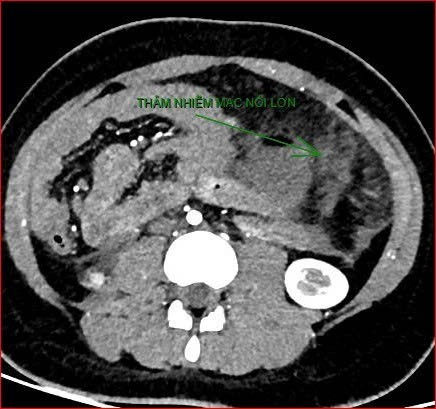

Khoảng 21 giờ 40 phút, kết quả chụp cắt lớp vi tính cho thấy tình trạng bệnh rất nặng và hiếm gặp, gồm: xoắn dạ dày, nhồi máu thận trái, nhồi máu lách, viêm đầu tụy, viêm hỗng tràng kèm dịch ổ bụng và tràn dịch màng phổi, trên nền bệnh nhân có hội chứng Down và tim bẩm sinh.

Hình ảnh chụp cắt lớp vi tính thể hiện tình trạng bệnh nhân rất nặng, hiếm gặp.